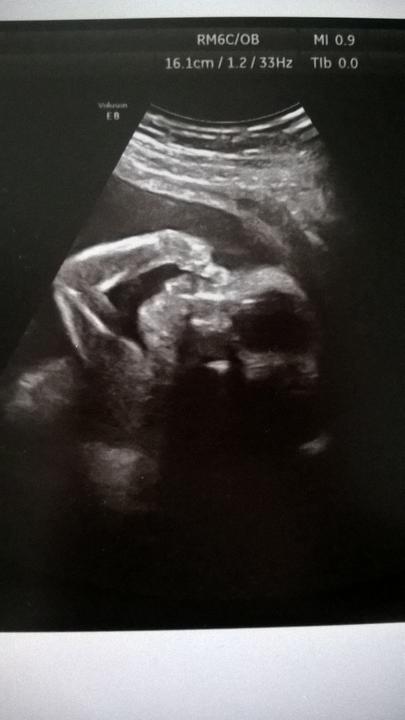

Dnes 80 dní hlásí koník a kontrola v Podolí úplně v pořádku (28+4) , chlapečci jsou zdraví,průtoky paráda, rostou nám ☺ Víteček už 1077g a Davídek 795g, diskrepance klesla na 26% což je nádhera a těší mě to😘 akorát větší má hodně plodové vody(depo 8,8 a má mít kolem 4,5) , nějak netusim co to ale znamená,zda je to taky riziko porodu...

Poslední den šestého měsíce, cesta z Podolí a já jsem šťastná =) Klukům se krásně vede, Vítek má už 902 g a Davídek 634 g, rostou oba i když menší je pomalejší ale prý se průtoky zlepšily a nyní je vše v pořádku =) Dneska jsem se už dozvěděla kdy cca přijdou na svět, prý když přejdeme 30 tt a budeme rodit ve 32 tt tak to bude super, tudíž se nesmí nic zhoršit a do půlky července je máme na světě, dál nás prý nenechají kvůli tomu menšímu.

Z dnešní kontroly (24+4) jsem nesvá🤰vsechny prutoky naprosto v poradku,coz je super ale Davidek uz ma rust.diskrepanci 33%, Vitek ma 711g a Davidek pouze 476g 😐 dlouzí jsou nejak stejne jen Davidek je pry hubeňour ☺ uvidime co pristi tyden,ale hrozi nam píchaní kortikoidů, no lezet se mi tam ted nechce ale nic jineho nam nezbyva😐kazdopadne mi doktor rekl ze kluci pujdou ven brzo, kdyz bude vse takhle tak do 34tt jdou ven,nedejbuh driv,coz take hrozi pokud se prutoky opet zhorsi,achjo🤰🏼

Tak dneska kontrola 22+4 kluci jsou naprosto v poradku, veskere prutoky take,coz je skvela zprava 😊a mensi Davidek roste tak jak ma i kdyz je mensi,stale diskrepance 28%🤰Davidek 368g a Vitecek 507g 🤰cipek ukazkovy a kila navic v míře😁

Tak holky, na dnešní kontrole ve 21tt velky screening,nechtěl se nám ukázat ani jeden,musela je paní Hanulíková pozlobit aby mohla změřit veškeré hodnoty s chlapečci jsou v pořádku až na toho menšího,stále ma hraniční průtoky v hlavičce,stále hrozí rozvoj izoimunizace a už je o 28% menší ,má 263 g a větší má 368g , sice přibírají oba a doktorka mě uklidňovala, že vše umí řešit,ale také že pokud se to nebude zlepšovat do 30tt tak mrňousci pujdou ven☹ nějak mě to dostalo☹